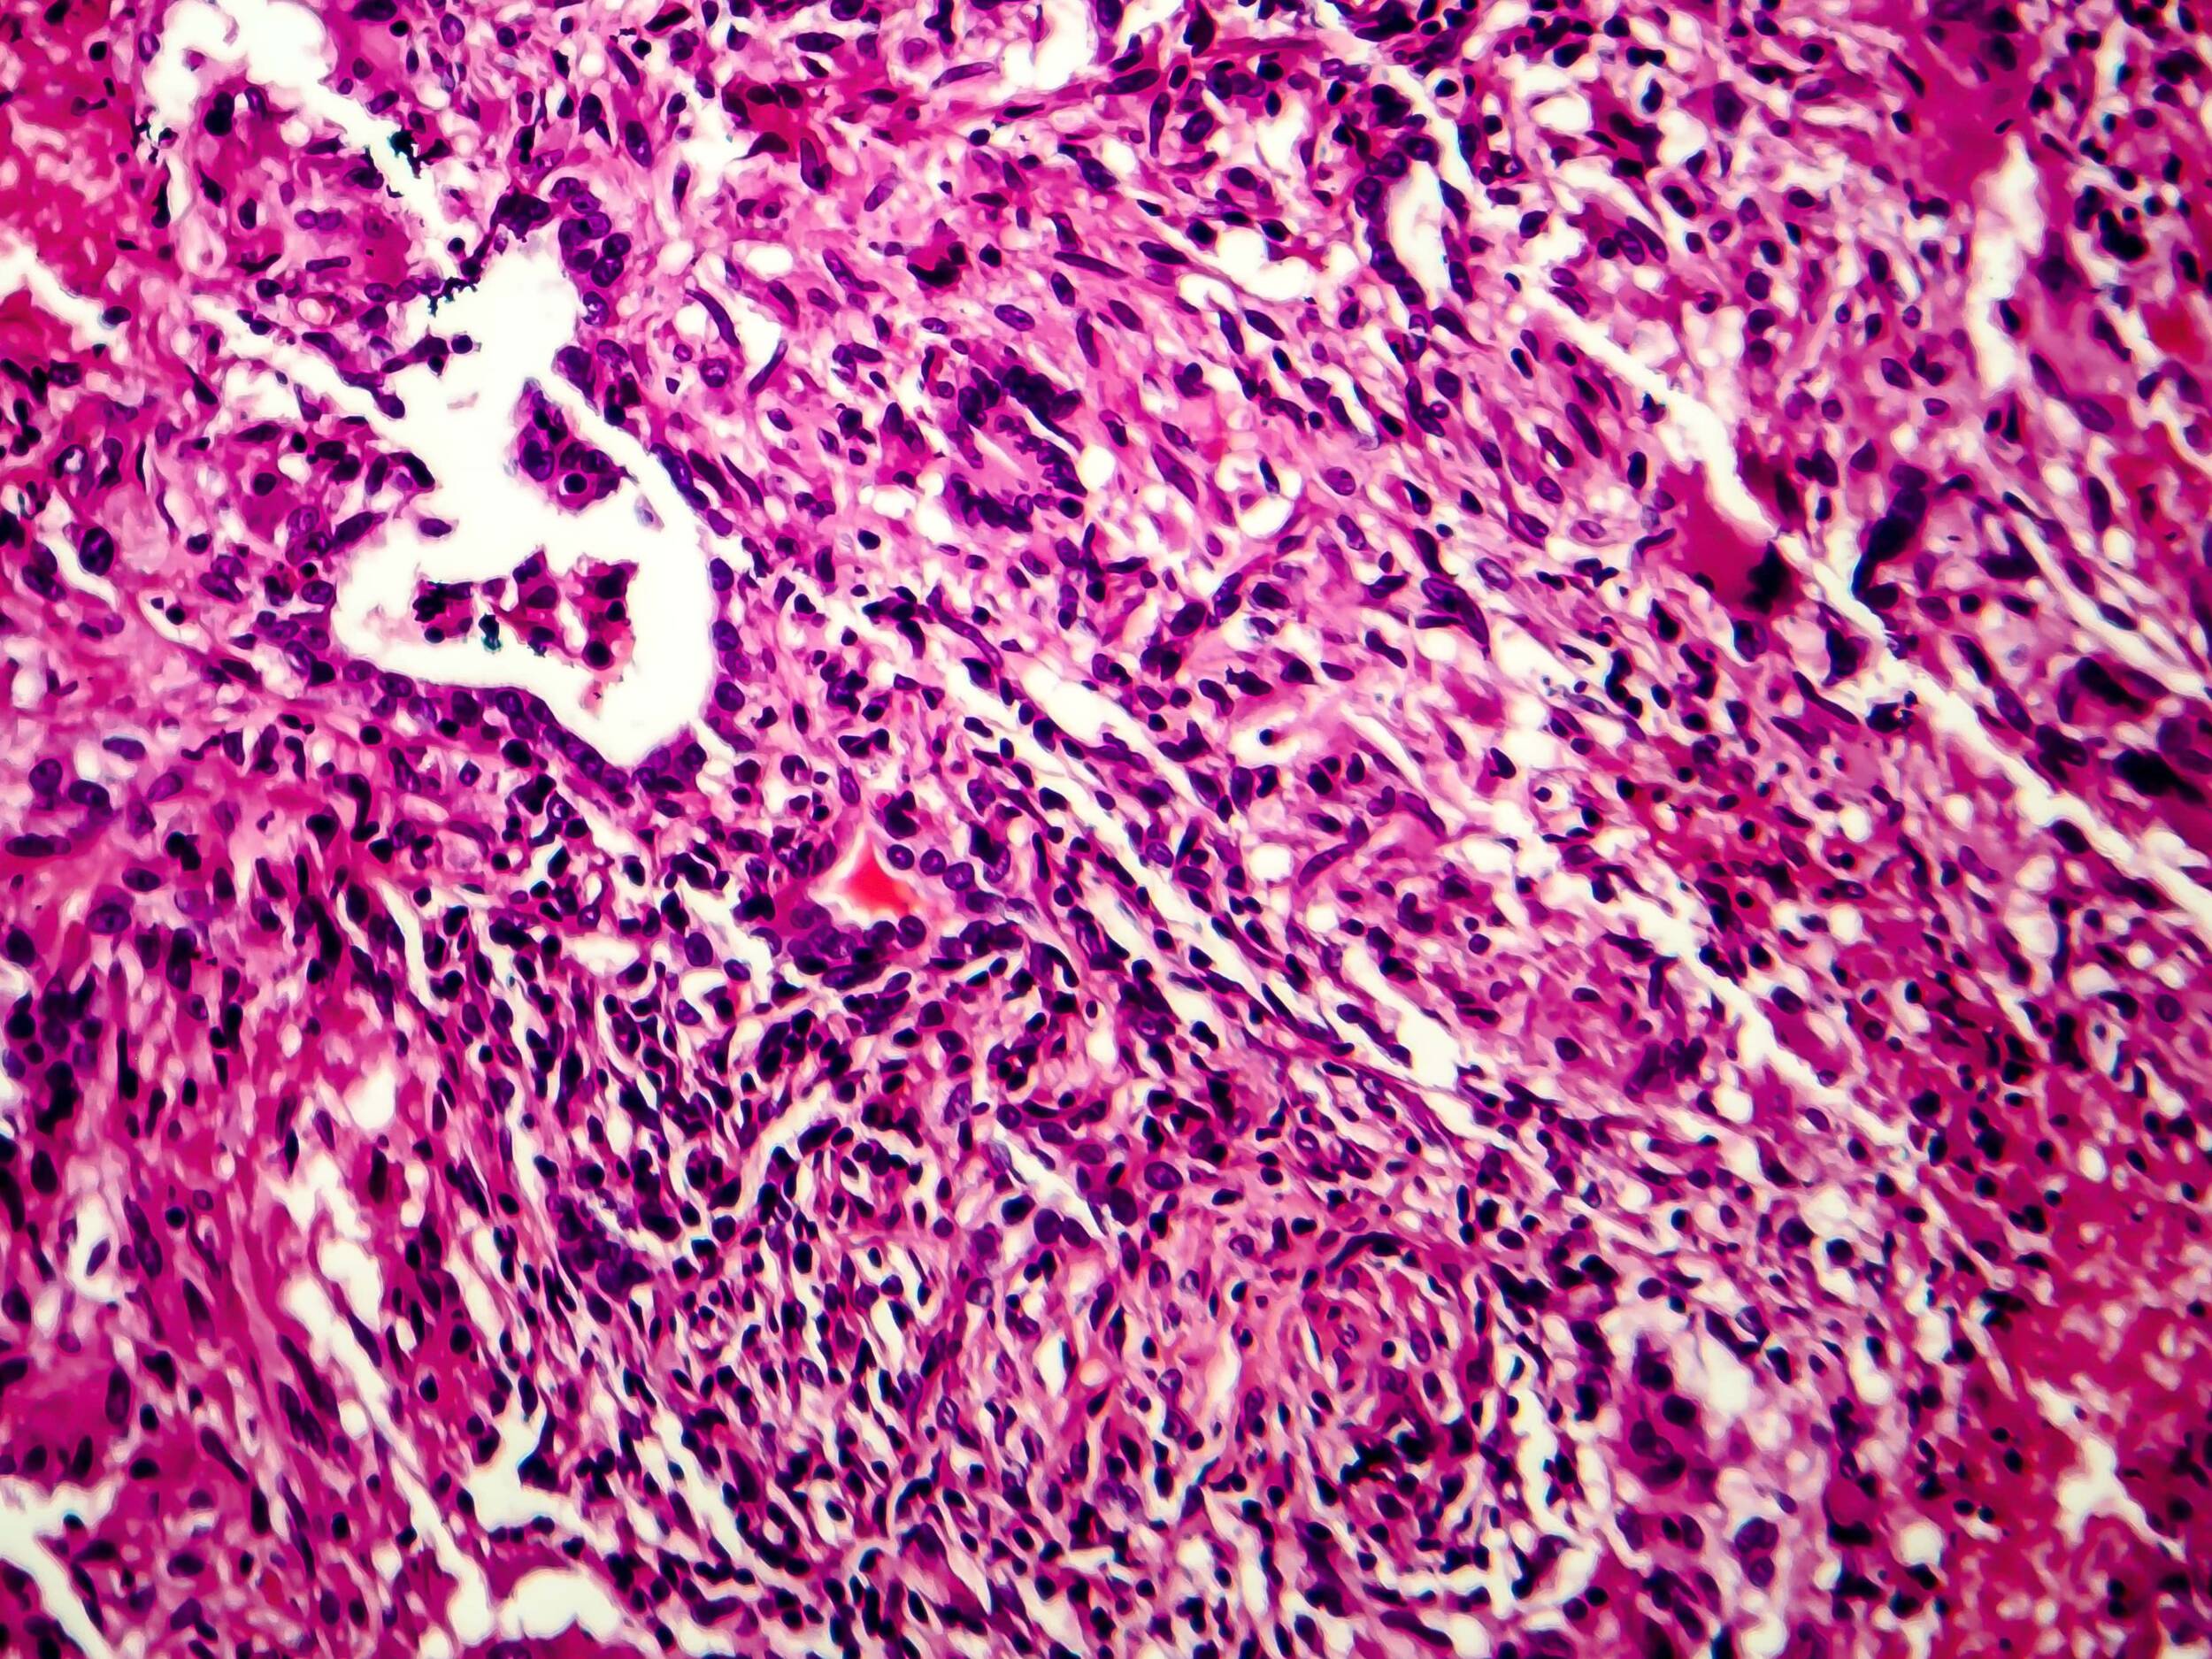

Krankheitserreger: Kulturen des Erregers der Menschentuberkulose